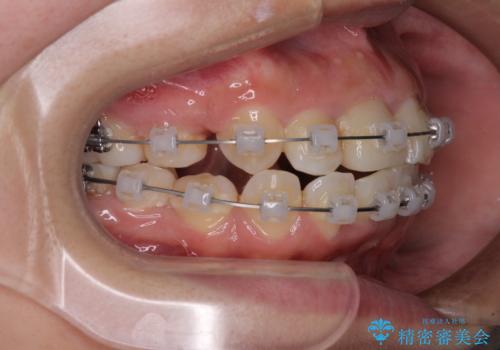

- 矯正装置

- クリアブラケット

- 治療期間

- 2年

矯正治療を行う前に、根管治療の必要な上顎前歯と下顎大臼歯の根管治療を行い、矯正治療の途中で下顎の欠損部にインプラント埋入することとし、矯正治療後に補綴治療を行うこととしました。